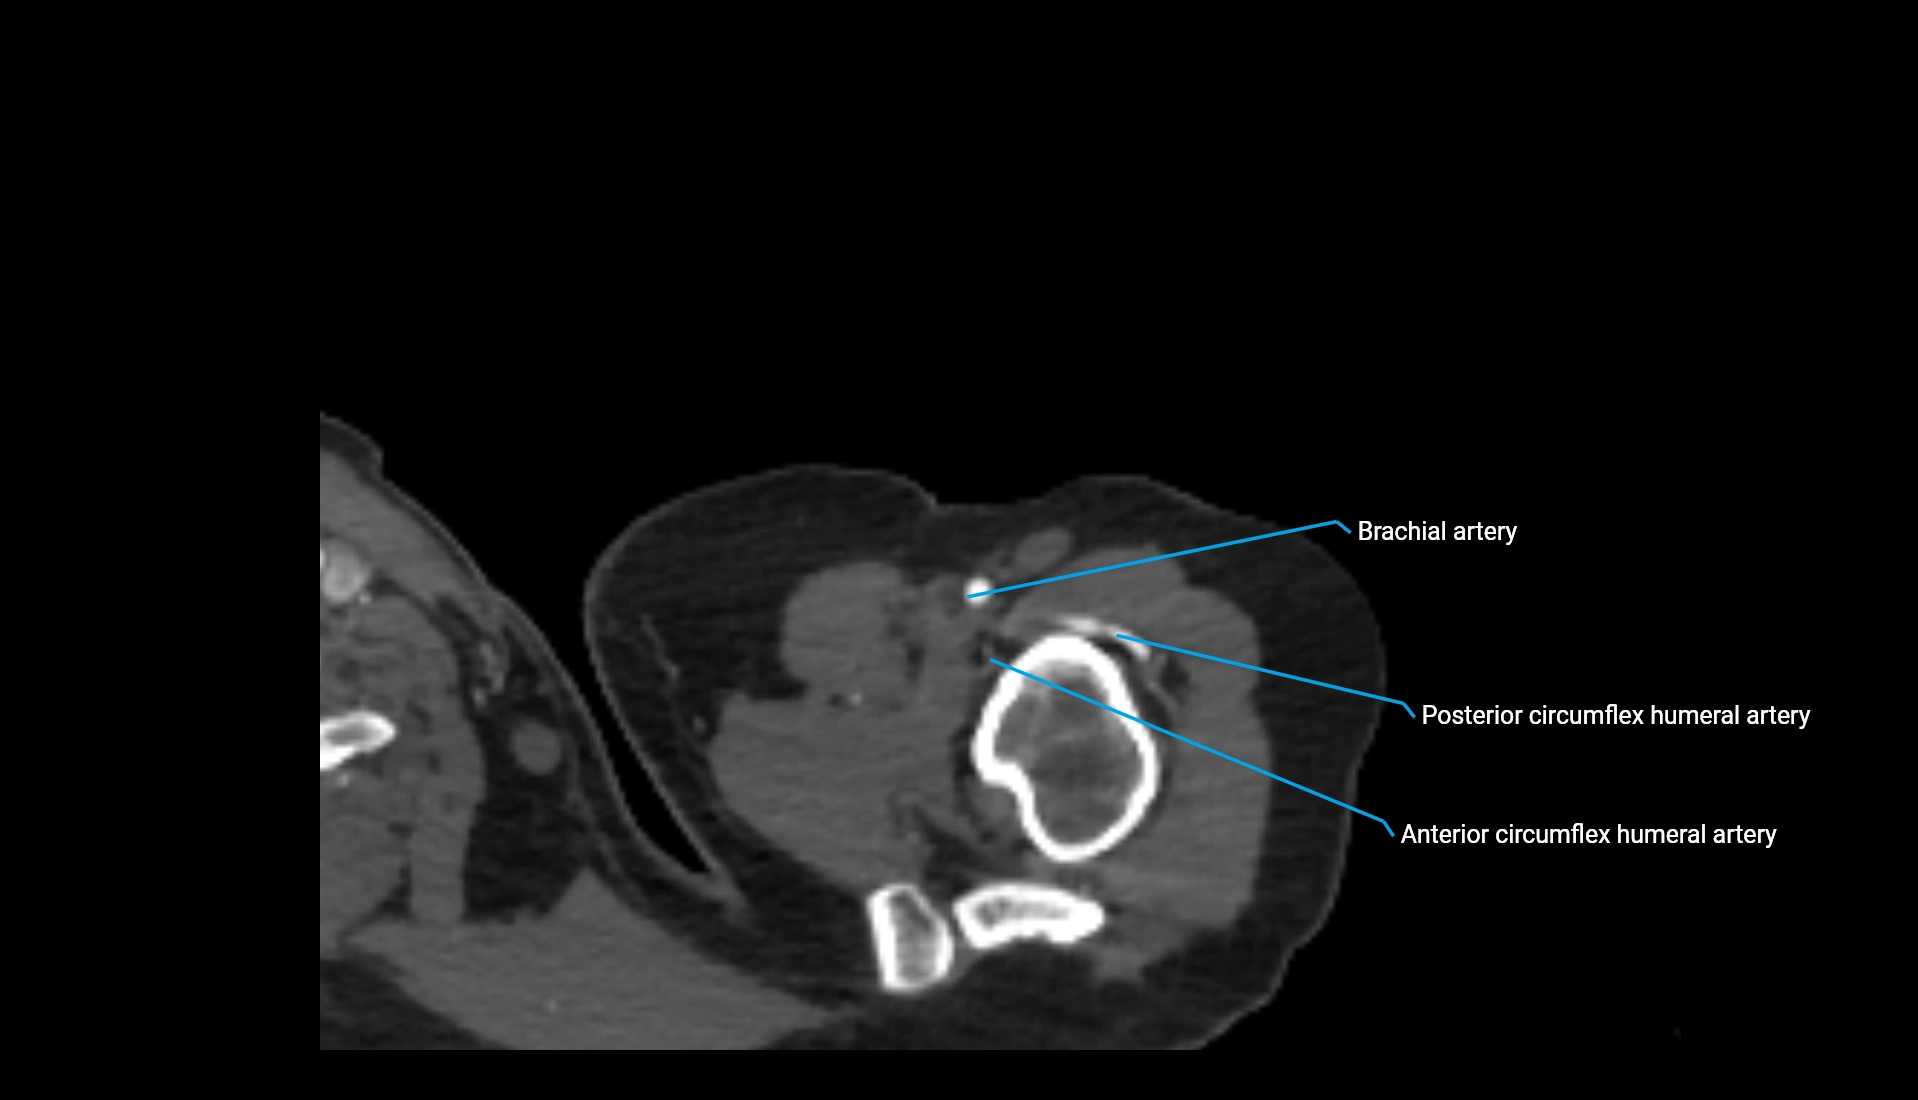

CT Appearance

Non-Contrast CT:

• Cortex: High-density, sharply defined

• Subchondral bone: Dense cancellous matrix

• Articular surface: Smooth concave contour articulating with the capitellum

• Excellent for evaluating bone integrity, alignment, and subtle fractures